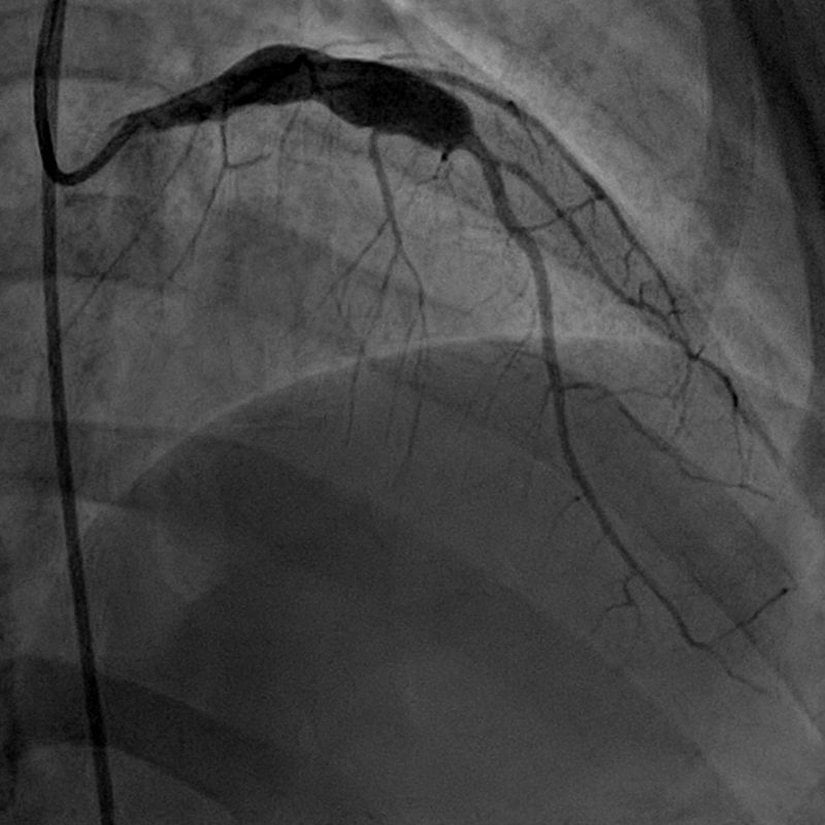

Kawasaki hastalığı, en çok koroner damarlar olmak üzere, vücuttaki orta çaplı atardamarlarda anevrizmalara (balonlaşma) neden olabilen, daha çok yenidoğan ve 5 yaş altı (kaydedilen vakaların %75'i 5 yaş altı çocuklardır) çoğunlukla erkek çocuklarda görülen akut sistemik vaskülittir. Bu hastalık, tıp literatürüne ilk kez, 1967'de Tomisaku Kawasaki adında bir Japon çocuk hastalıkları uzmanı tarafından kazandırılmıştır.

Deri döküntüleri (enantem), konjunktivit , ellerde ve ayaklarda şişme, boyundaki lenf düğümlerinde büyüme ile karakterize semptomlarından dolayı ilk olarak hastalık "mukokutanöz lenf düğümü sendromu" olarak isimlendirilmiştir.Genellikle tedavi edilmediğinde hayatı tehdit edebilen koroner arteriyel anevrizmalar (CAA) ile ilişkili akut koroner arterite neden olur.

- Ve en ciddi olarak koroner arter anevrizmalarının (CAA) gelişmesidir.

- D. Cuevas. (2019). Giant Coronary Aneurysms In Kawasaki Disease. Radiopedia. | Arşiv Bağlantısı